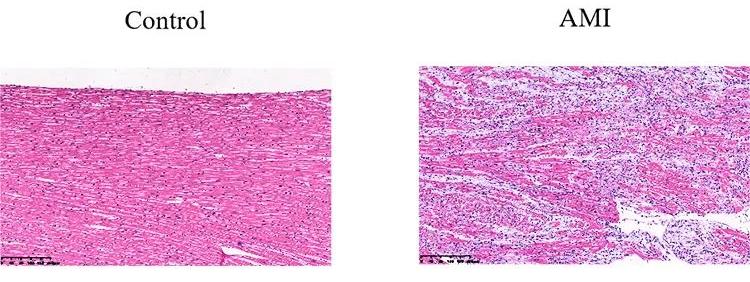

檢測指標:病理學HE染色和免疫組化分析心肌損傷。

病理HE染色示意圖

心肌梗死動物模型